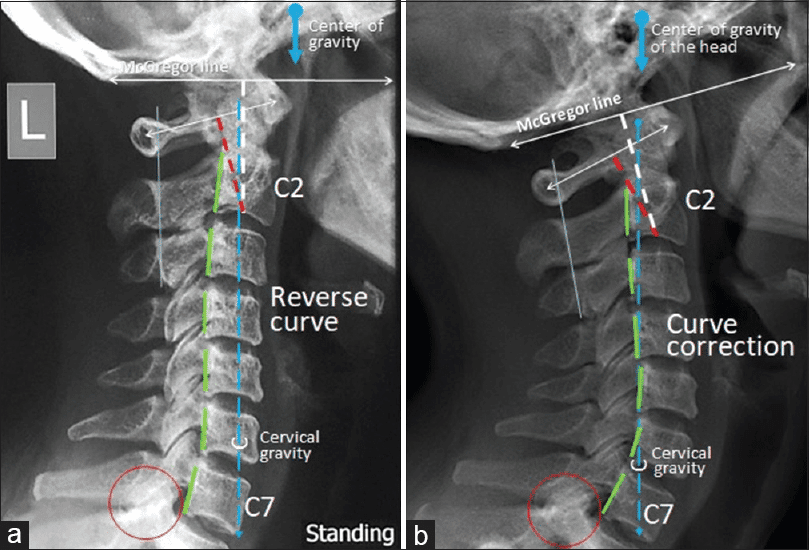

• Digital X-ray evaluation